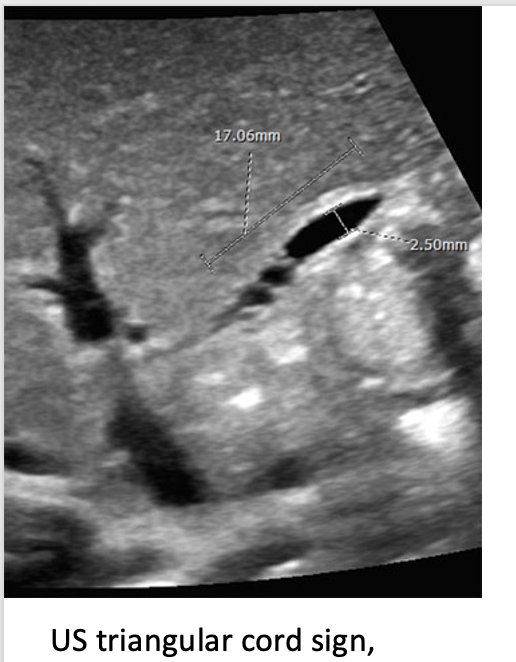

5

17

Q

this is associated with situs inversus or polysplenia/asplenia

A

biliary atresia

18

cirrhosis and death within 3 years if no liver transplant performed